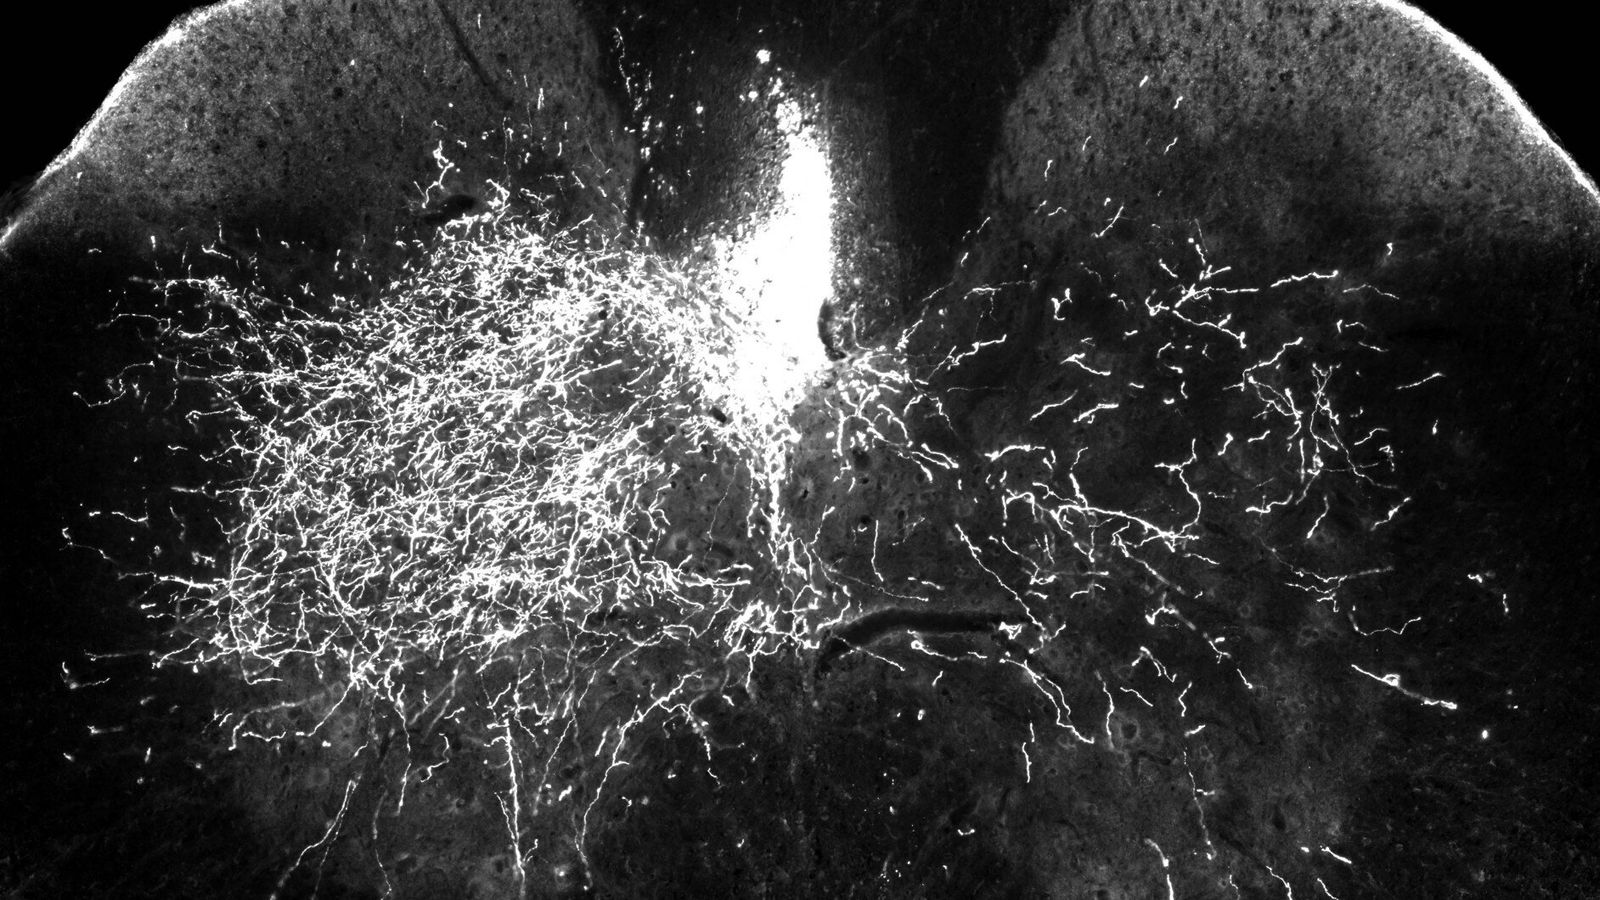

Research team identifies potential target for restoring movement after spinal cord injury – Medical Xpress Friday, 20 December, 2019 Medical Xpress